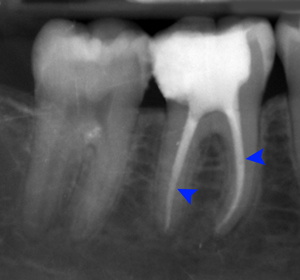

Illustration for the procedure for Root Canal Treatment When nerve or blood supply of the tooth is infected because of decay or an injury, root canal treatment is performed with the help of specialized instruments. Root canal treatment is done to save natural teeth. It is absolutely painless procedure and is performed under local anesthesia. After Root Canal Treatment is completed, a full coverage crown is placed on that particular tooth so as to maintain & protect its function. Ar Sweet Smile we can achieve perfect Root Canal Treatment as we use most advance equipments like RVG - Digital X-Ray on Big Screen and Apex locator, which gives the accuracy of Root Canal Length up to 0.5 mm. |